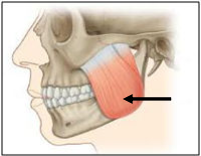

Os músculos da mastigação trabalham junto com a articulação temporomandibular para realizar todos os movimentos possíveis da mandíbula. Qual é o nome do músculo indicado pela seta na figura a seguir?